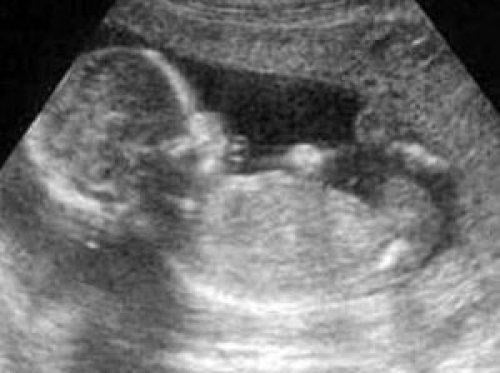

ÇOCUKLARIN KIZ MI OĞLAN MI DOĞACAĞI BİLİNMEZDİ-O yıllar, ultrason cihazlarının bilinmediği yıllar. Çocukların cinsiyetleri doğumdan önce bilinemezdi. Her anne baba, her ağabey abla, yeni doğacak bebeğin cinsiyetini doğum anına kadar merak ederdi. Bebeğin cinsiyeti, doğumdan hemen sonra ilk aons edilen bilgi olurdu.